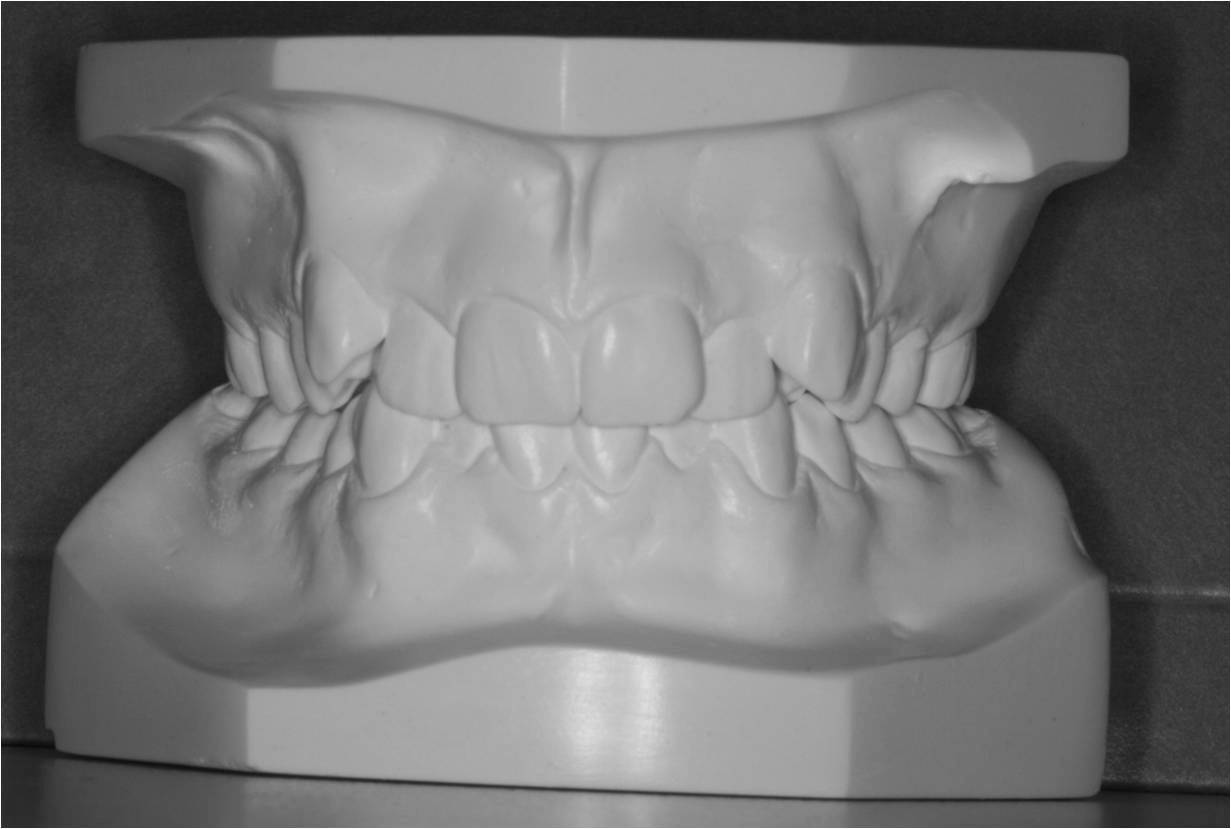

Første gang dit barn besøger Tandreguleringsklinikken, bliver der lavet studiemateriale.

Studiemateriale, består af modeller, fotos og røntgenbilleder af tænder og ansigt. Der bliver også udleveret et helbredsskema, som skal udfyldes på stedet. Det er vigtigt at vide, om jeres barn er sundt og raskt, eller om der er særlige hensyn, vi skal tage - eksempelvis til medicin med videre.

Anden gang dit barn kommer på Tandreguleringsklinikken, er det for at snakke med den specialtandlæge, der har lavet den gældende behandlingsplan. Specialtandlægen forklarer, hvad problemet drejer sig om, og med hvilken bøjle dit barn kan få rettet tænderne.